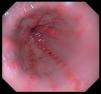

He was admitted to the hospital with an episode of blood in stool and evidence of anemia. Endoscopic study revealed vascular-like lesions in antrum converging as they neared the pylorus, compatible with watermelon stomach1,2 (Fig. 1). In the presence of active bleeding, he was treated with argon plasma coagulation3 (Fig. 2).

At the present time, we are unable to avoid its development and, given the presence of bleeding, the treatment with the best results is endoscopic, including the use of laser ablation, argon plasma coagulation or cold. With respect to the possible surgical solution, like antrectomy, it can be utilized if other therapies fail.9,10 There are medical treatments if endoscopy cannot be performed, but they are usually associated with more severe adverse effects.